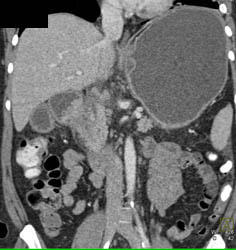

Gastric Cancer at Gastroesophageal (GE) Junction With Celiac Nodes